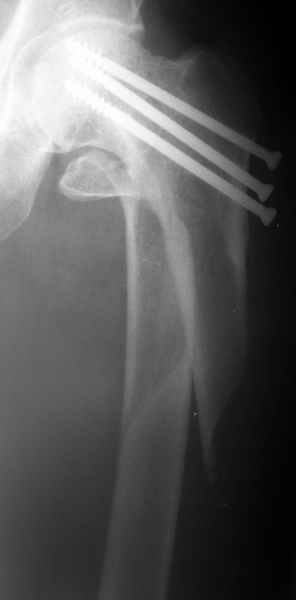

Alexander Chelnokov 21 Январь 2004, 09:05

1

Вчера оперировали - винты удалены через 1 прокол. Затем выполнили закрытый интрамедуллярный остеосинтез без расверливания бесканальным гвоздем 13 мм (реконструкционного для нее не нашлось). Гвоздь заперт статически - в проксимальный отломок 3 винта 6 мм, в дистальный - 1.

Учитывая варус сросшейся шейки, постарался вальгизировать проксимальный отломок, насколько гвоздь позволил. Результат в приложении. Картина перелома видна лучше, чем на начальных снимках.

Интересно, что линия перелома не выходила на отверстия от винтов, а была кзади. Комментарии?

The screws were removed through a stab wound. Then a closed insertion of an unreamed solid nail 13 mm was performed and the nail statically locked - 3 screws 6 mm in the proximal fragment and 1 in the distal.

Considering varus of the healed neck i tried to get some valgus to the proximal fragment as the nail allowed. The result attached. The fracture pattern can be seen better than in the initial films.

Any comments?